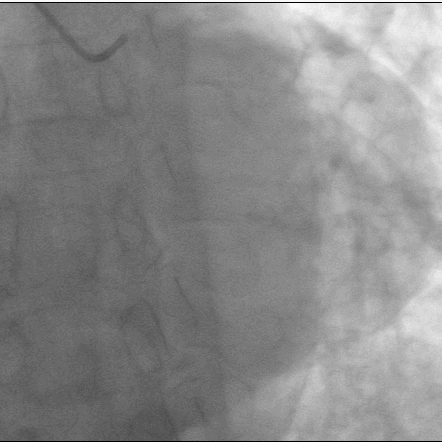

造影:

造影可见,LAD中段狭窄90%,伴有弥漫钙化影,LCX中段次全闭塞,RCA中段60%狭窄,决定先行处理左冠。面对钙化弥漫病变,该病例又将采取什么样的手术方案呢?